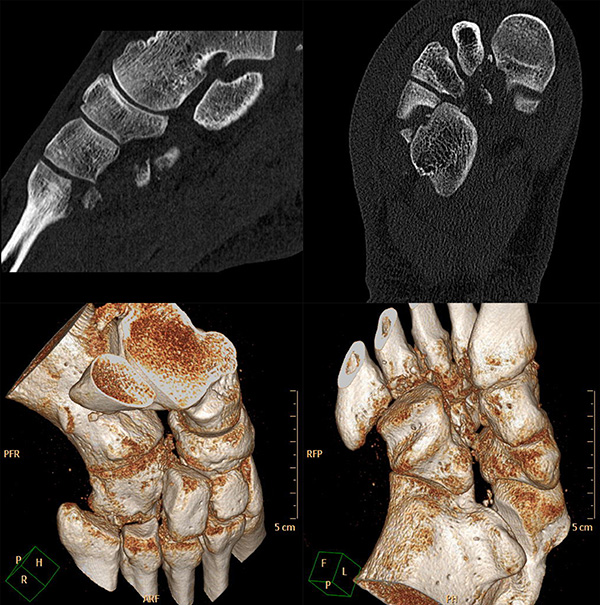

Bei Verdacht auf eine Lisfranc-Verletzung sollte daher die Indikation zur Computertomographie (CT) mit multiplanaren Rekonstruktionen großzügig gestellt werden. Hier können auch diskrete Dislokationen und kleine Fragmente gut dargestellt werden. Auch bei Nachweis einer Lisfranc-Verletzung sollte stets ein CT zur Suche nach Begleitverletzungen sowie zur Planung der weiteren Therapie angefertigt werden 9751164 (Richter 2007).

Zum Lesen der Bildbeschreibung und zur Vollansicht bitte das Bild anklicken.